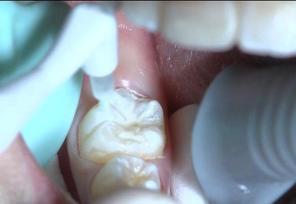

4.涂布封闭剂: 用小毛刷或专用器械,蘸取适量封闭剂涂布在干燥的牙面上。要使封闭剂充分渗入窝沟点隙中,可用小毛刷引导。注意封闭后的窝沟点隙中不能留有气泡。

去年12月,7岁的佳佳在家长的陪同下来到两江二院口腔科做检查。家长告诉李仁文医生,佳佳 比较喜欢吃零食 ,很担心她有蛀牙。 李医生检查后,发现佳佳的口腔状况尚好,但磨牙合面窝沟深,建议她做个窝沟封闭。与她俩沟通后,李医生为佳佳行窝沟封闭术,先清洁牙面、酸蚀,再涂布窝沟封闭剂。